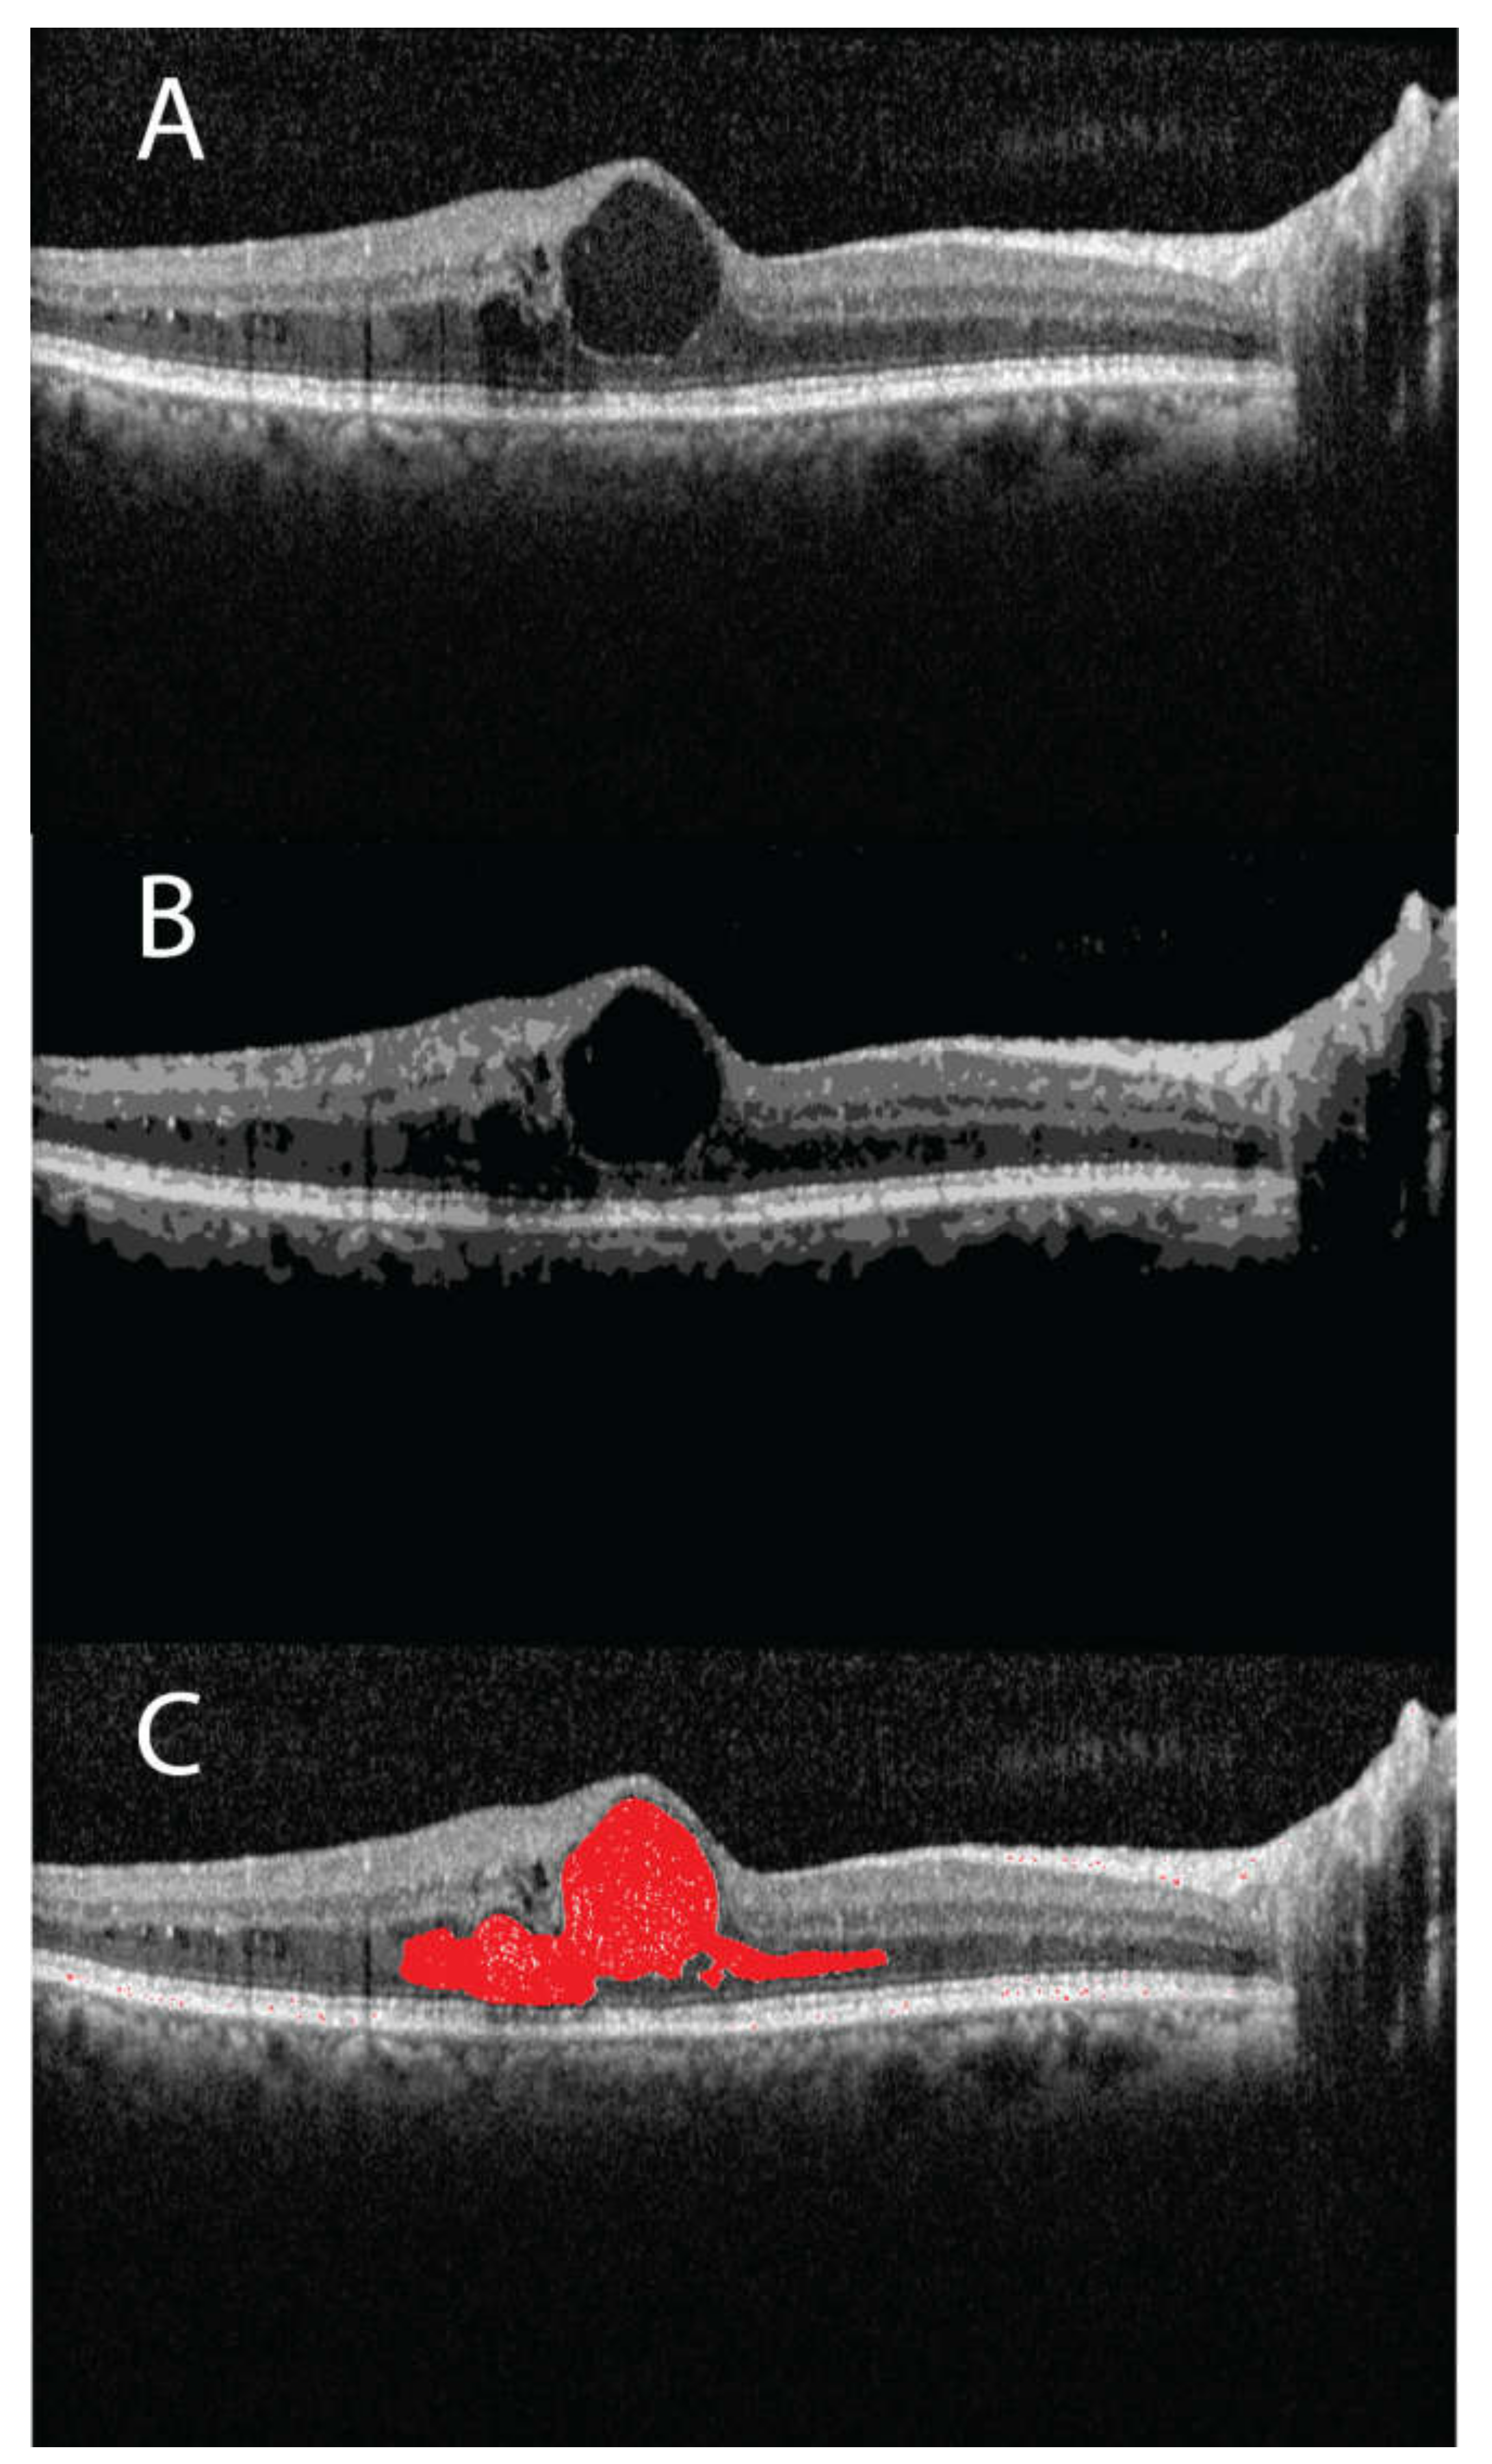

The CFT and edema volume were significantly correlated (r = 0.40, p < 0.001) as shown in the linear regression data (Figure 1). Similarly, the linear regression data of CFV and TRV were significantly correlated with the edema volume (r = 0.41 and 0.65 respectively, p < 0.001 (Figure 2 and Figure 3)). Interestingly, the estimated zero edema volume CFT (Figure 1) was 386.06 μm, which was very close to the median CFT of the 19 eyes with an absence of edema. Similarly, the zero edema volume CFV (Figure 2) was 0.30 mm3, which was very close to the median CFV of the same 19 eyes. In case of TRV, the difference between the two was slightly greater (9.06 mm3 from Figure 3 versus 10.1 mm3 in the 19 eyes). Figure 4 shows a sample B-scan (A), after SNR balancing, (B) with the segmented edema regions overlaid on (A).

Figure 4.

(A) A sample B-scan of a patient (categorized as recurrent and with an ETDRS grading as PDR) showing fluid filled regions; (B) the same B-scan is shown after signal to noise ratio balancing; (C) segmented fluid region is highlighted in red.